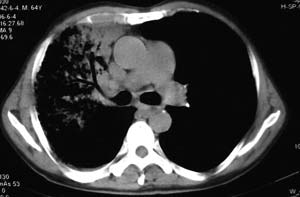

右侧胸廓略小于左侧,右肺上叶大片实变影,近肺门处密度较高,内见支气管气相,周围较淡,呈网格状,余肺野清晰,纵隔内见肿大淋巴结,右侧胸腔少量积液。临床 咳血,咳痰 发热 , 血象1.2万。

考虑大叶性肺炎。

右侧胸阔塌陷,纵隔右移。右上肺大片状高密度影,沿支气管血管束走行,内见点状钙化;支气管充气征阳性,支气管呈柱状扩张;胸膜下小叶间隔增厚;右侧后胸壁内侧见带状水样密度影;纵隔淋巴结增大。

考虑:①右上叶陈旧性结核合并感染可能大。②右侧少量胸水。

影像表现:肺窗示右肺上中叶均可见小片、条索状、小结状密度增高影,可见支气管充气相,小叶间隔增厚,支气管通畅,余肺未见明显异常。纵隔窗示4r可见小淋巴结融合,无明显肿大,右侧示少量胸腔积液。